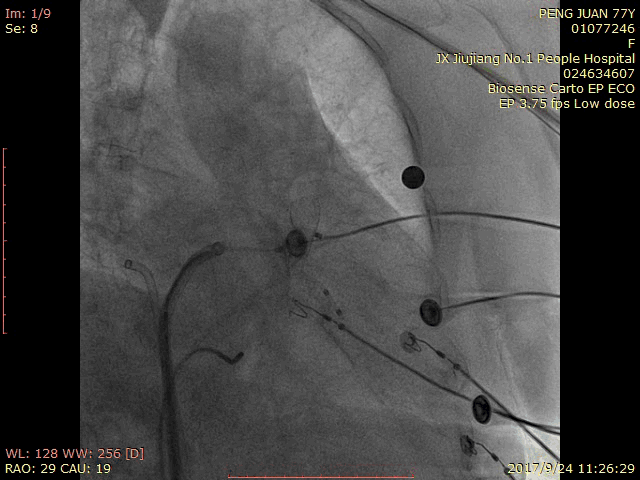

术中造影:

RAO 30 CAU 20:

RAO 30 CAU 20 Fish Ball造影:

RAO 30 CAU 20 牵拉试验: